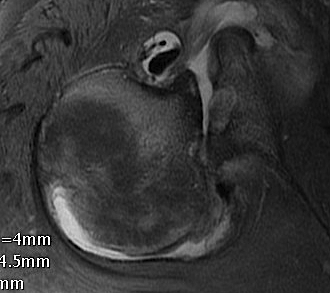

MRI

Acute MRI demonstrating reverse Hill Sachs and posterior labral tear

Chronic posterior shoulder dislocation with humeral head remodelling and glenoid bony deficiency

Case 1: Lesser tuberosity osteotomy, removal comminuted articular fragment, insertion osteochondral allograft

Case 2: Osteochondral allograft with anchor repair of subscapularis